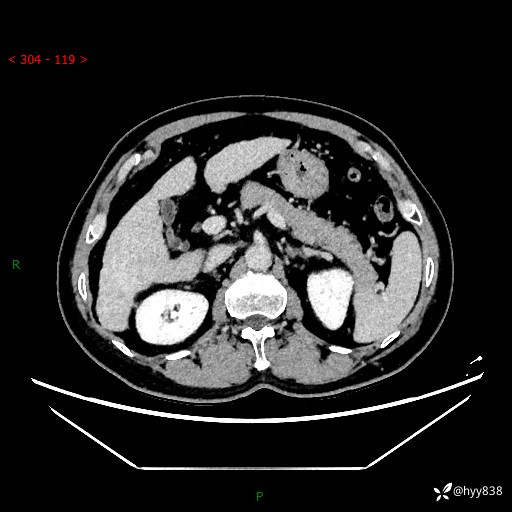

延迟期